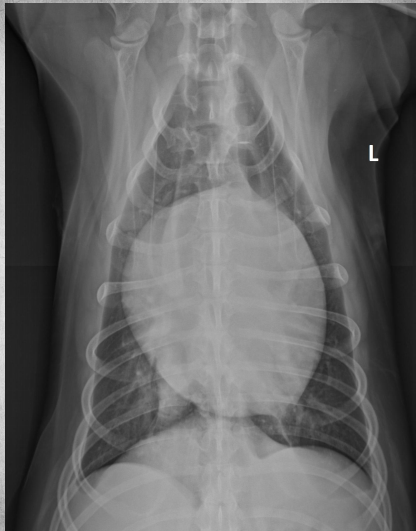

● Female feral cat

● Respiratory distress after handling

diaphragmatic hernia + pregnancy before day 45

● 3 yo male neutered cat

● Increased respiratory rate

● Lethargy

free fluid, pleural effusion = FIP

dorsal lung margins pushed away from thoracic wall

pericardial fat stripe also tells you its fluid and not fat around the heart